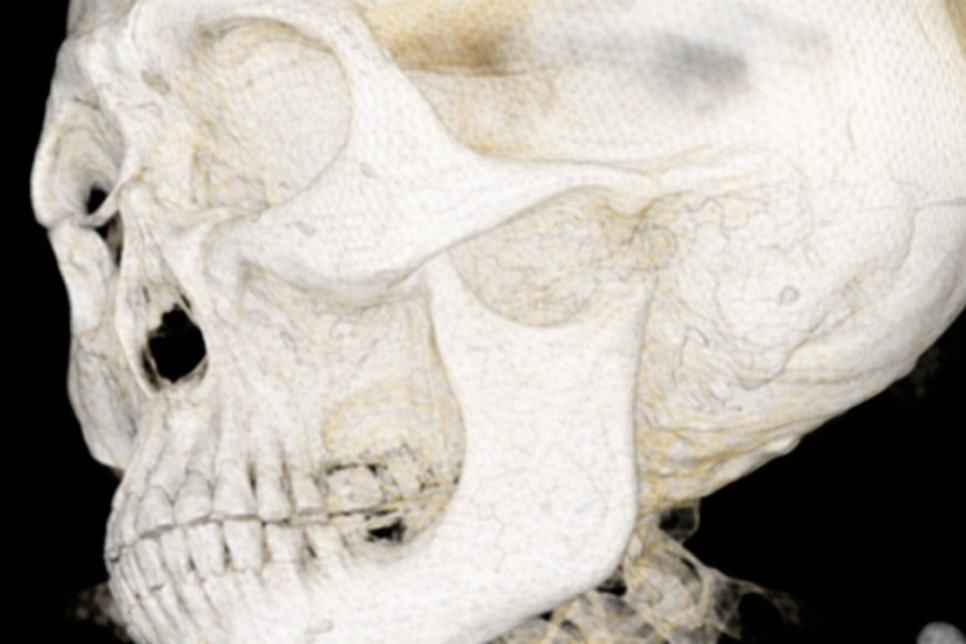

앞서 선유도역 치과 에서 설명해 드린

Panorama와 CBCT 방사선 사진과

구강 스캔본을 정합하면,

구내와 주변 구조를 한 번에 파악할 수 있는

좋은 자료가 만들 수 있습니다.

그럼 이제 정합한 자료를 바탕으로

시뮬레이션을 진행합니다.

선유도역 치과 예시 사진처럼

구강 내 환경과 해부학적 구조물을

한눈에 볼 수 있습니다.

이를 바탕으로 어디에 픽스처를 심으면 좋을지

알맞은 위치를 선정합니다.